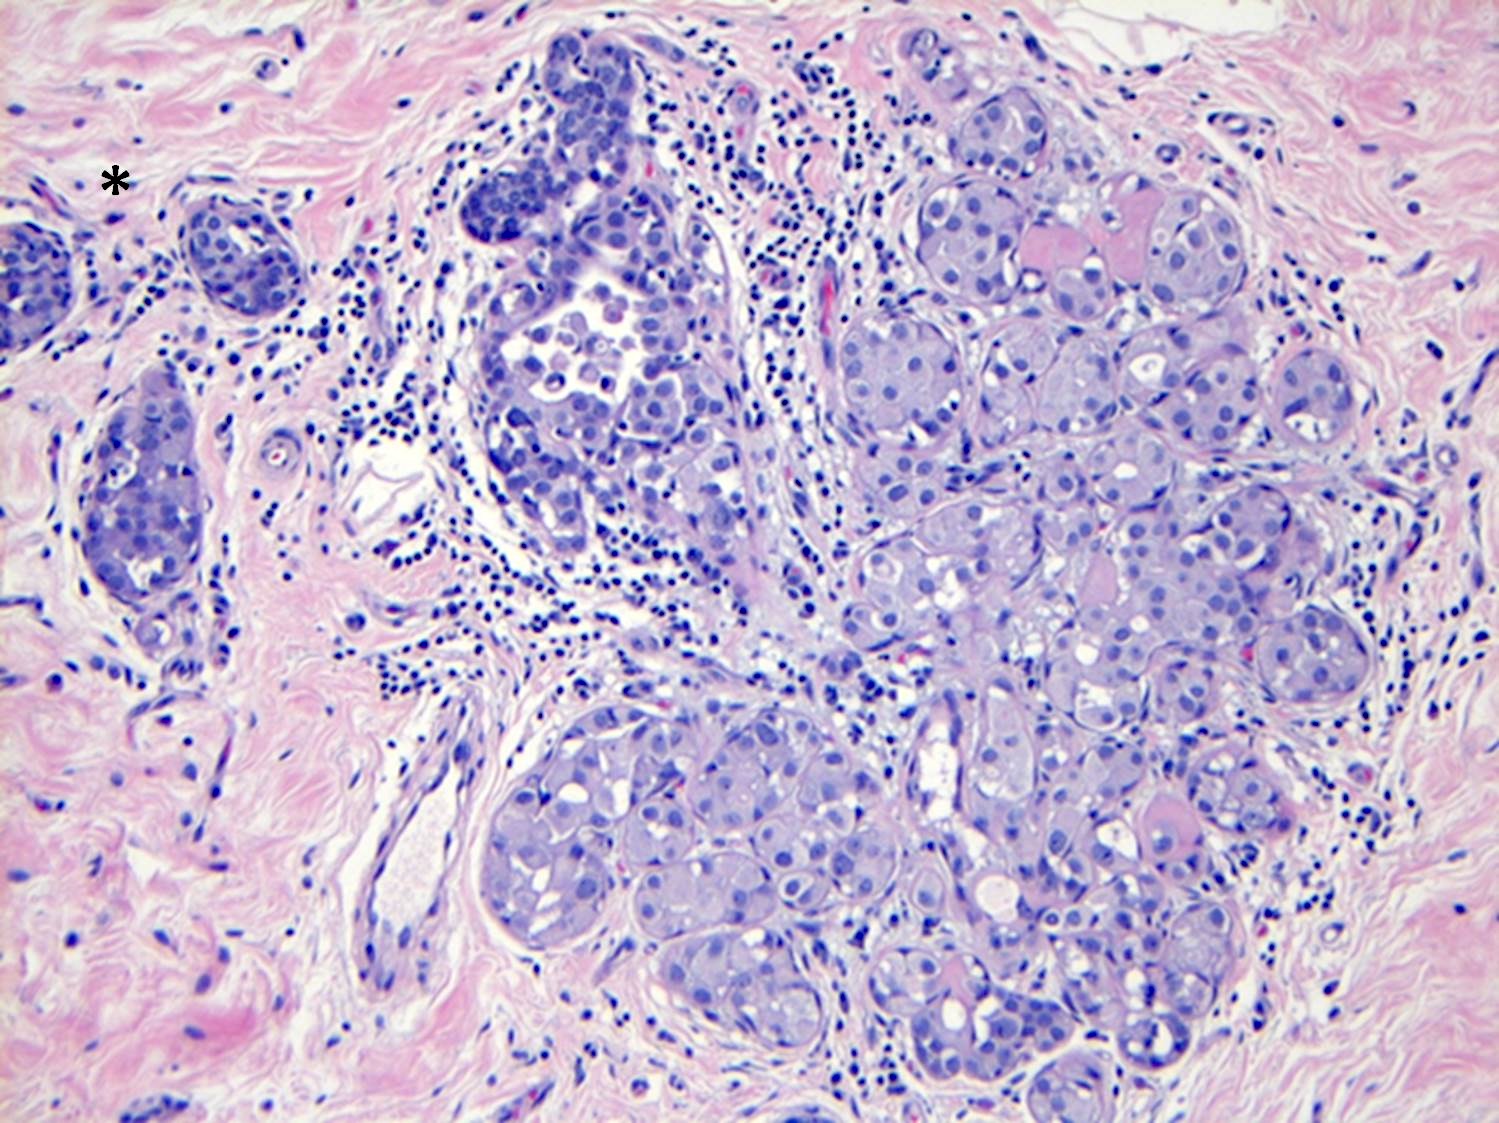

- LCIS most often involves lobules but may also grow along the basement membrane of ducts (i.e., pagetoid spread)

- Pagetoid spread in ducts is the characteristic growth of cells between luminal and myoepithelial layers of a duct without destroying ductal epithelium or filling up ductal lumina

- Often makes the ducts appear convoluted; this is called a cloverleaf pattern

- LCIS may secondarily involve (or arise in) sclerosing adenosis, radial scar, fibroadenoma, collagenous spherulosis or papilloma

- Rosen triad: the presence of tubular carcinoma, columnar cell lesions and LCIS / ALH

- Classic LCIS cells are monomorphic, evenly spaced, loosely cohesive and do not show polarization or gland formation

- In almost all cases of LCIS, at least some cells contain intracytoplasmic vacuoles or lumina, which may contain an eosinophilic globule; this feature is not specific to LCIS

Microscopic (histologic) images

Contributed by Anna Biernacka, M.D., Ph.D.